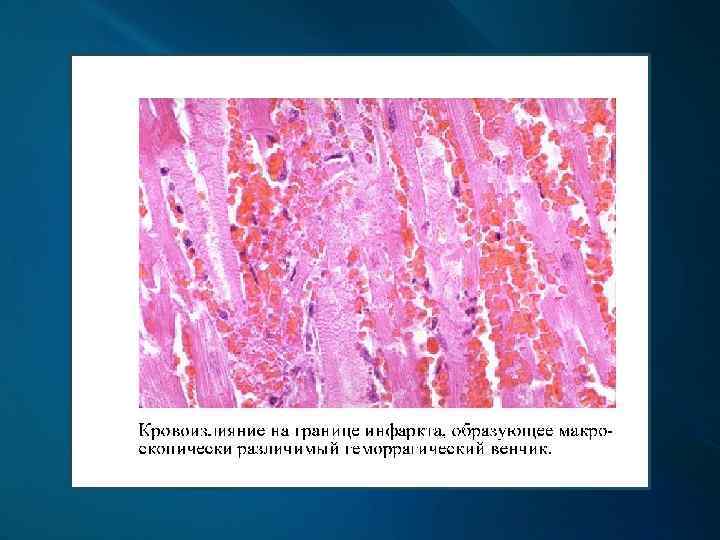

Макроскопически: первые часы - миокард дряблый, неравномерно кровенаполнен; через 18 -24 ч. – четко виден некроз; конец 1 -х сут. – некроз глинистокрасноватый, выбухает из-за отека, с геморрагическим венчиком; к 4 -6 сут. и далее – некроз западает, плотный, желто-серый, с красной каймой грануляционной ткани вокруг; через 3 -5 нед. – рубец красновато-серый, затем белесовато-серый.